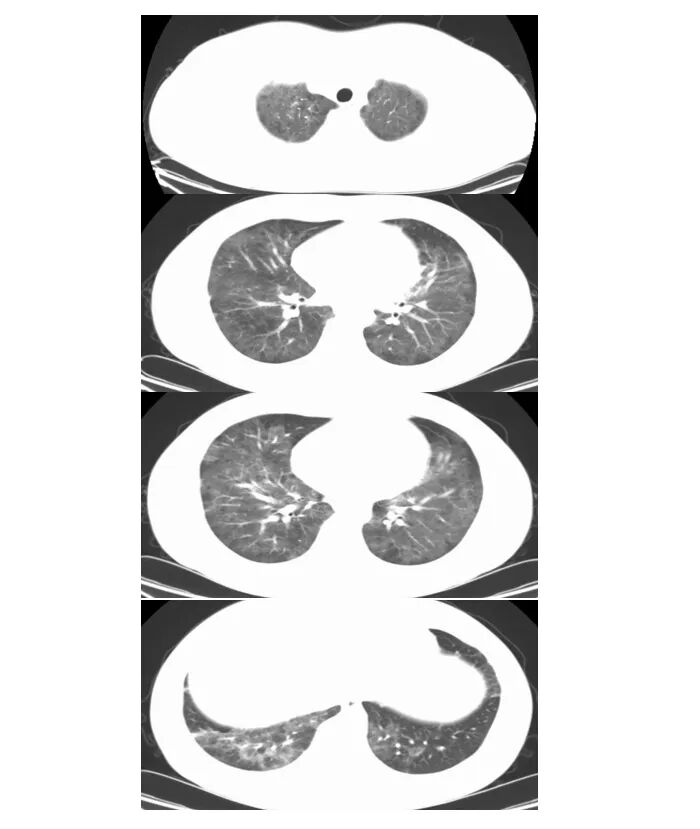

2024年12月23日胸部CT:双肺感染性病变,较前明显减少

12月27日胸部CT:1.双肺多发感染性病变,病灶较前略减少。2.双肺下叶多发间质性改变,较前略减轻。

2024年12月27日胸部CT:双肺弥漫性病变